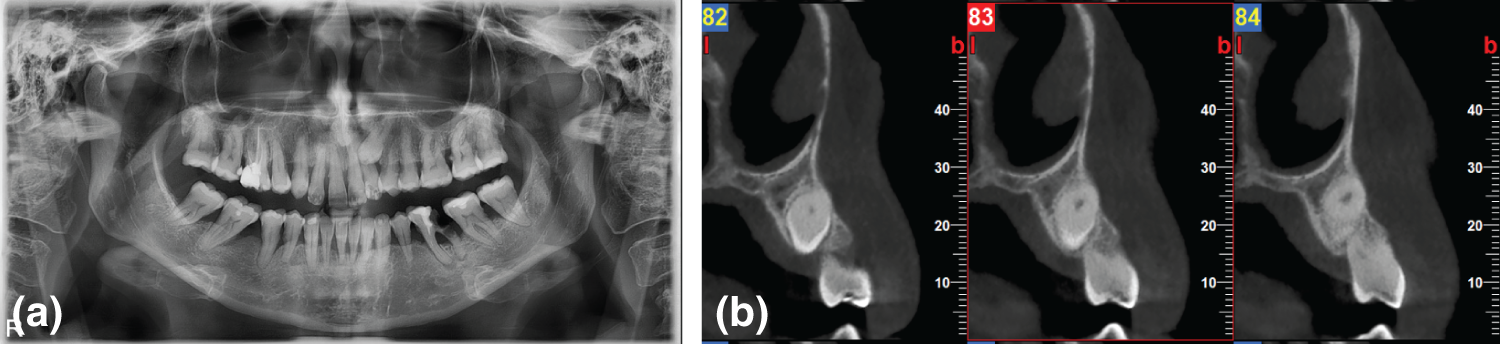

A 67-year-old non-smoker male presented for gingival hyperplasia at a private periodontal dental office. His medical history included a kidney transplant ten years ago, and he is currently on a-blockers, mycophenolate mofetil, prednisolone, felodipine and cyclosporin. As known, both Ca channel blockers and cyclosporin can cause gingival hyperplasia [7], [8]. It has also been supported that the severity of hyperplasia depends on the concentration of the drugs and the combination of more than one drug that causes hyperplasia, in that case, cyclosporin and Ca channel blocker (Fig. 1a).

Fig. 1. (a) Baseline picture, (b) Surgical treatment of gingival hyperplasia combined with extraction of part of the impacted tooth. The arrows indicate the bone needed to be removed in order to extract part of the impacted #13, (c) CBCT reveals that the impacted tooth #13 has no periodontal ligament suggesting that the tooth is ankylosed, and (d) Reevaluation, clinical presentation of surgical treatment and placement of provisional restoration in the maxilla.

The patient was scheduled for steps 1, 2 and 3 of periodontal treatment. Step 4 was periodontal surgery, including gingivectomy and open flap debridement. At the same time, part of the ankylosed impacted tooth #13 was extracted. The apical part of the root was not extracted since the extraction would have created a severe osseous defect. During the surgery, an odontogenic cyst that was mesial to the impacted tooth was also removed, and guided bone regeneration was attempted with allograft, xenograft and collagen membrane (Fig 1b). The CBCT revealed an odontogenic cyst and an impacted canine #13. (Fig 1c). The patient tolerated treatment well and was scheduled for dental implant placement in 6 months. Unfortunately, the patient discontinued treatment due to medical reasons.